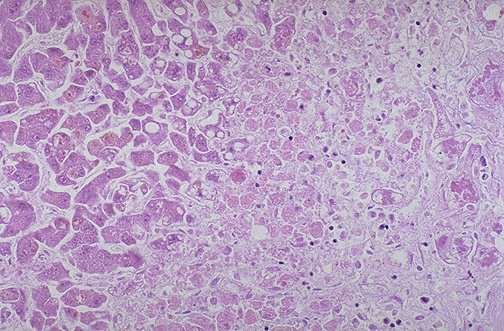

| There is extensive hepatocyte necrosis seen here in a case of acetaminophen overdose. The hepatocytes at the right are dead, and those at the left are dying. This pattern can be seen with a variety of hepatotoxins. Acute liver failure leads to hepatic encephalopathy. |